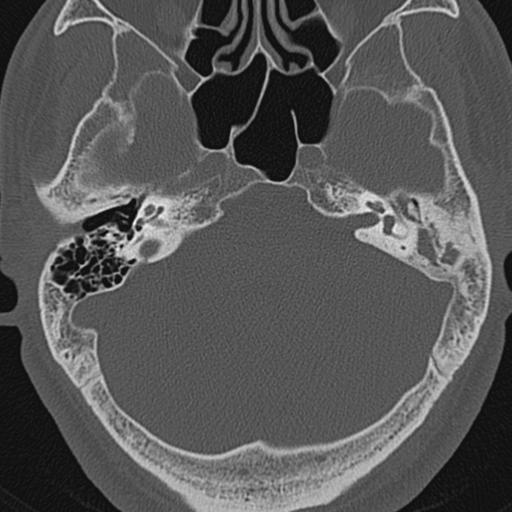

以下是引用zxl51642在2009-8-25 13:37:00的发言:[br]1、左侧慢性硬化型中耳乳突炎(中耳鼓室腔及听小骨受累),并胆脂瘤形成;2、左侧外耳道软组织密度影填塞,考虑炎性肉芽肿,建议结合临床;3、右侧颈静脉窝较左侧明显扩大,不排除颈静脉球瘤,建议mr进一步检查。

以下是引用随光逐影在2009-8-25 19:05:00的发言:[br]1)左侧慢性中耳乳突炎(肉芽肿或胆脂瘤形成),左侧外耳道炎性肉芽肿。2)右侧颈静脉球高位。